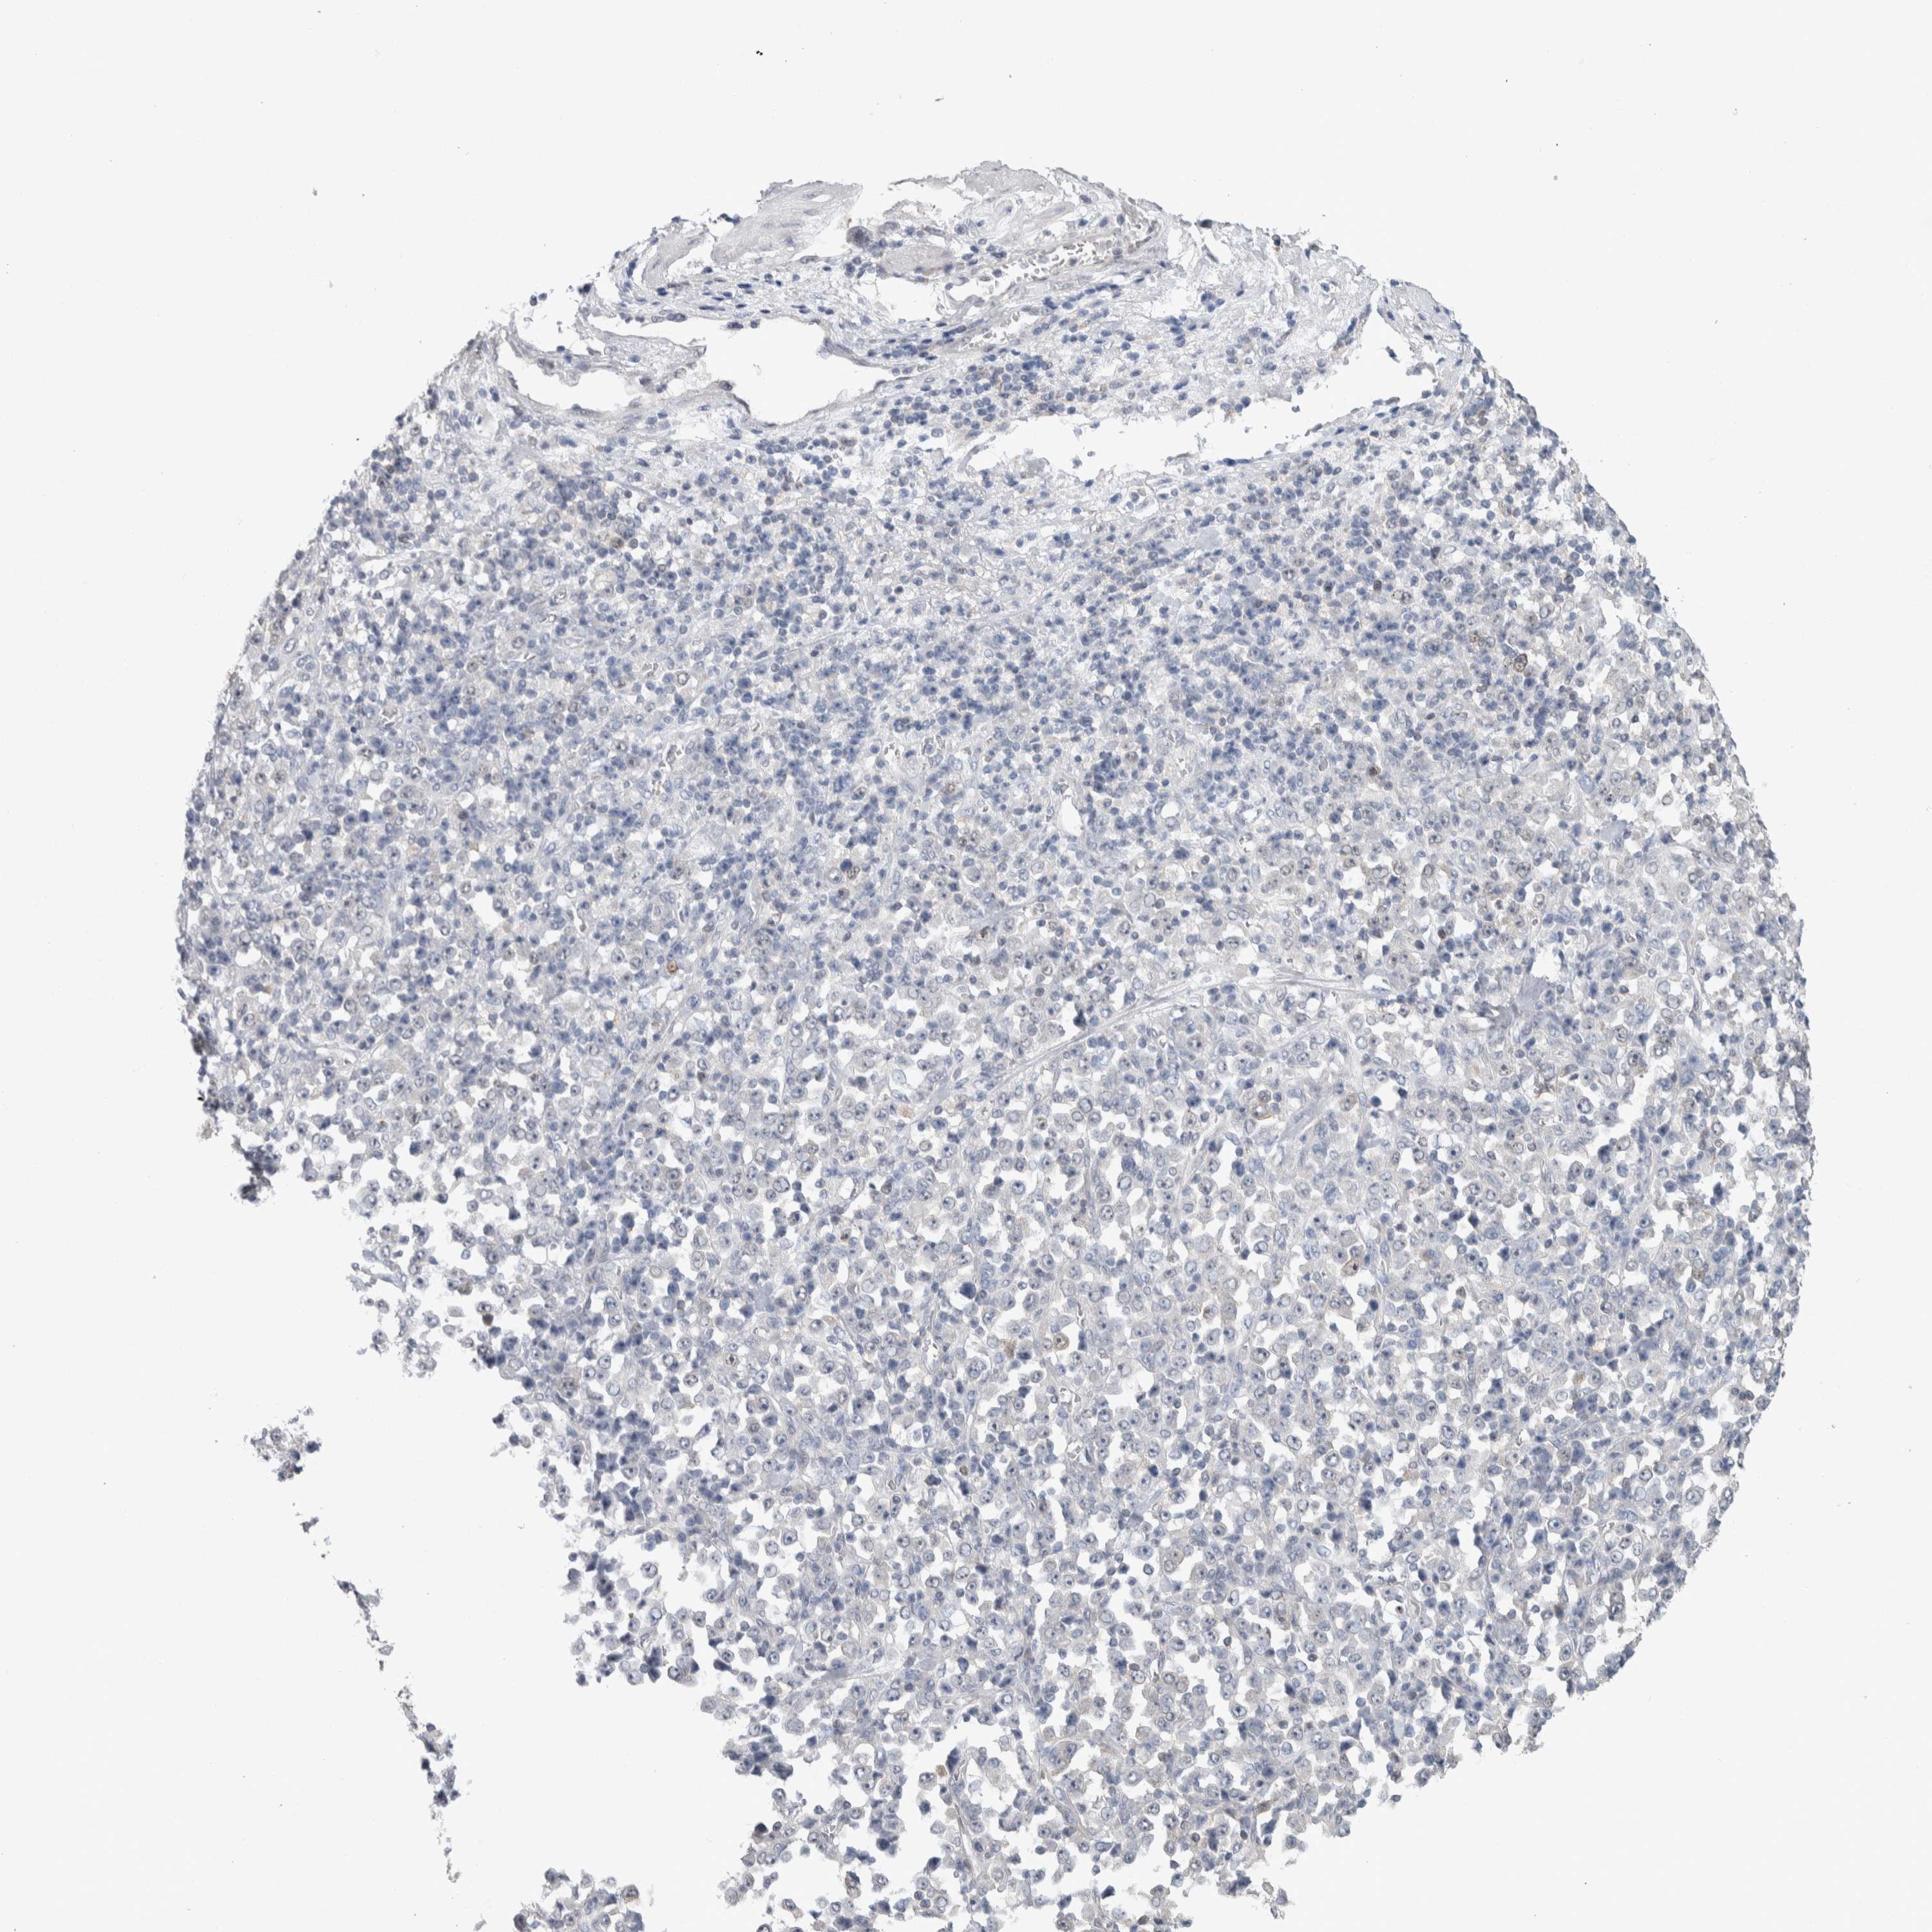

STOMACH CANCER - Protein expressioni

A mouse-over function shows sample information and annotation data. Click on an image to view it in a full screen mode. Samples can be filtered based on level of antibody staining by selecting one or several of the following categories: high, medium, low and not detected. The assay and annotation is described here.

Antibody stainingi

Antibody staining in the annotated cell types in the current human tissue is reported as not detected, low, medium, or high, based on conventional immunohistochemistry profiling in selected tissues. This score is based on the combination of the staining intensity and fraction of stained cells.

Each image is clickable and will lead to virtual microscopy that enables deeper exploration of all samples and also displays staining intensity scores, fraction scores and subcellular localization as well as patient and tissue information for each sample.

Antibody HPA024432

Staining

High

Medium

Low

Not detected

Intensity

Strong

Moderate

Weak

Negative

Quantity

>75%

75%-25%

<25%

None

Location

Nuclear

Cytoplasmic/membranous

Cytoplasmic/membranous,nuclear

Adenocarcinoma, NOS